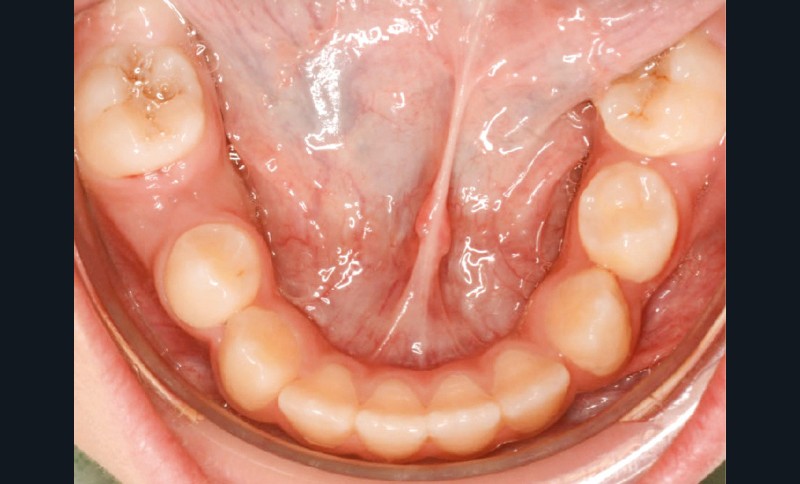

Lina, 8 ans et 5 mois, nous est adressée en consultation d’orthodontie dans le service de médecine bucco-dentaire de l’Hôpital Bretonneau en transfert avec absence des 2 prémolaires du secteur 1, alors que 44 et 45 sont présentes et que cette dernière manque de place pour faire son évolution sur l’arcade (fig. 1 et 2).

Un bilan radiologique 3D (Cone Beam CT) est prescrit dans le but d’évaluer, avec l’équipe de chirurgie du Dr Jean-Luc Charrier (Hôpital Bretonneau), la possibilité de transplantation d’une prémolaire du secteur 4 vers le secteur 1 et de définir le meilleur transplant possible entre 44 et 45. Sont analysées les dimensions du site receveur ainsi que l’anatomie, la position et l’état de maturation radiculaire des prémolaires candidates à la transplantation (fig. 3).